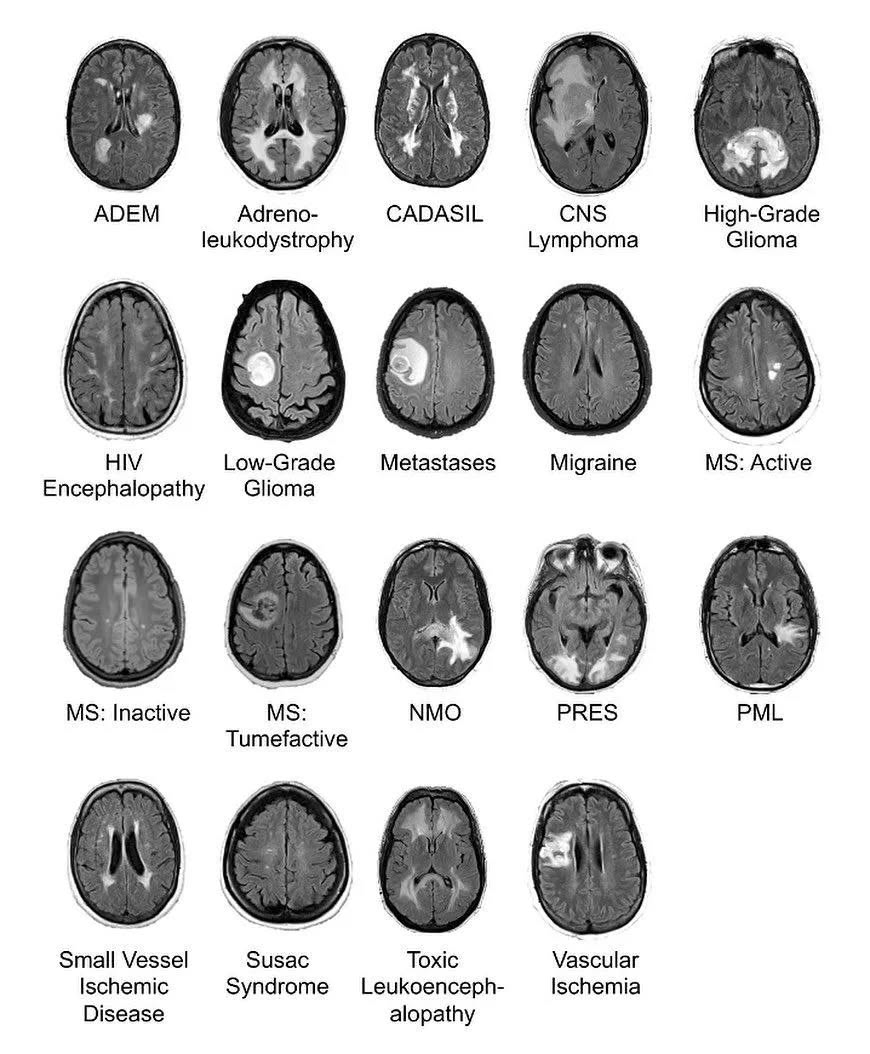

Common brain lesions on FLAIR MRI Fluid-attenuated inversion recovery (FLAIR) is an MRI sequence with an inversion recovery set to null fluids. For example, it can be used in brain imaging to suppress cerebrospinal fluid (CSF) effects on the image, so as to bring out the periventricular hyperintense lesions. The FLAIR sequence analysis has been especially useful in the evaluation and study of CNS disorders, involving: ● Lacunar infarction ● Multiple sclerosis (MS) plaques ● Subarachnoid haemorrhage ● Head trauma ● Meningitis and other leptomeningeal diseases @med_dreams0 Don't forget to follow #student #medical #hospital #doctors #newpost